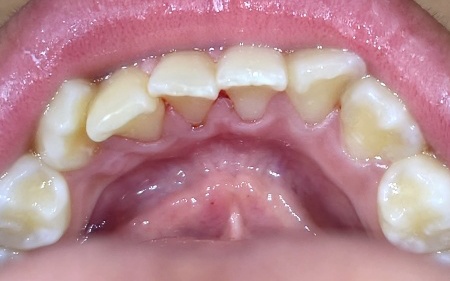

治療前

「下前歯に歯石がある」とご相談いただきました。

拝見したところ、下前歯の裏側に歯石が多く付着していました。

歯石は細菌の塊が石灰化して硬くなったもので、表面がざらざらしているため新たな汚れが付きやすく、通常の歯磨きだけで除去することは困難です。

このまま放置すると、虫歯や歯周病のリスクが高まるため、しっかりと取り除く必要があると診断しました。